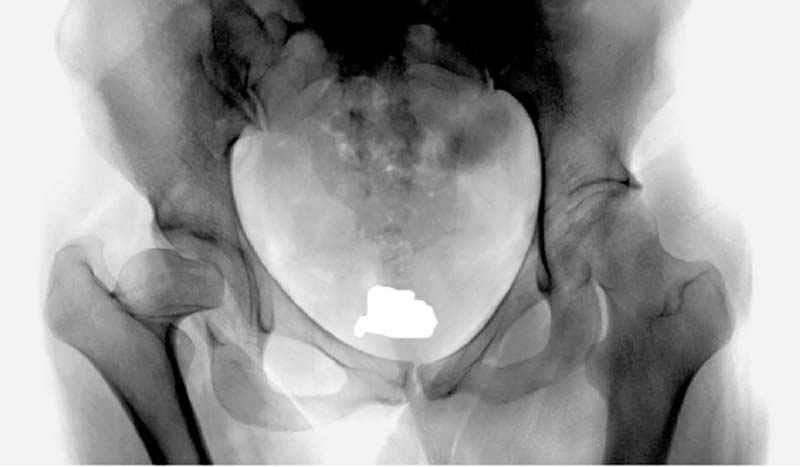

До настоящего времени считалось, что в одноопорном ортостатическом положении тазобедренный сустав функционирует как рычаг первого рода, таз удерживается в горизонтальном положении за счет отводящей группы мышц, а нагруженными являются верхние сектора головки бедренной кости и вертлужной впадины. Соответственно суммарная нагрузка на головку бедренной кости равна учетверенной массе тела (при условии, что плечо веса тела относится к плечу отводящих мышц как 1:3).Проведены экспериментальные исследования на трехмерной и плоскостной модели тазобедренного сустава, анализировались клинические, патоморфологические и интраоперационные наблюдения, изучен достаточный объем научных публикаций. Установлено, что в ортостатическом положении с опорой на одну ногу, а так же в средине одноопорного периода шага, тазобедренный сустав функционирует как рычаг второго рода. Это обеспечивается за счет натяжения связки головки бедра, которая ограничивает приведение бедра, наклон таза в неопорную сторону и разгружает отводящую группу мышц. Благодаря связке головки бедра происходит замыкание тазобедренного сустава во фронтальной плоскости, при этом основная нагрузка приходится на нижние сектора головки бедренной кости и вертлужной впадины. Согласно нашим приблизительным расчетам плечо силы реакции связки головки бедра относится к плечу веса тела как 1:3. Соответственно нагрузка на нижний сектор головки бедренной кости в одноопорном ортостатическом положении составляет в покое 2 веса тела. В качестве одного из наглядных доказательств можно привести иллюстрацию эксперимента на трехмерной модели тазобедренного сустава с аналогом связки головки бедра (Рис.1).

Мною произведены измерения на 290 рентгенограммах ТБС у молодых лиц обоего пола (средний возраст их 26.919 лет) без признаков патологии означенного сустава. Согласно точным расчетам плечо массы тела в среднем составило 107.685 мм (расстояние от центра головки бедренной кости до средней линии тела). Согласно тем же точным расчетам плечо силы реакции связки головки бедра равняется в среднем 35.190 мм (расстояние от центра головки бедренной кости до дна ямки вертлужной впадины, где прикрепляется проксимальный конец связки головки бедра). Соответственно плечо веса тела относится к плечу силы реакции связки головки бедра как 1:3,060, это если быть точным… Я допускаю, что есть проекционные искажения, эффект увеличения изображения на рентгенограмме, погрешности в измерениях, индивидуальная изменчивость размеров, быть может я недостаточное количество суставов обмерил, точку проксимального крепления связки головки бедренной кости на рентгенограмме не видно, а линия действия ОЦМ в одноопорном ортостатическом положении смещается от центра в сторону ТБС на разную величину, обусловленную антропометрическими особенностями и т.д.… именно поэтому в своем сообщении я указал соотношение 1:3, и назвал его приблизительным».